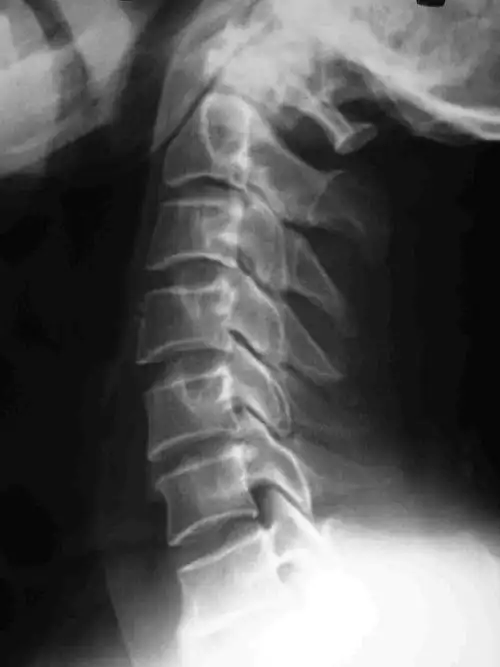

颈椎ct示:颈4-5骨赘增生严重颈椎磁共振示:脊髓严重受压,脊髓发白变性

颈椎ct片